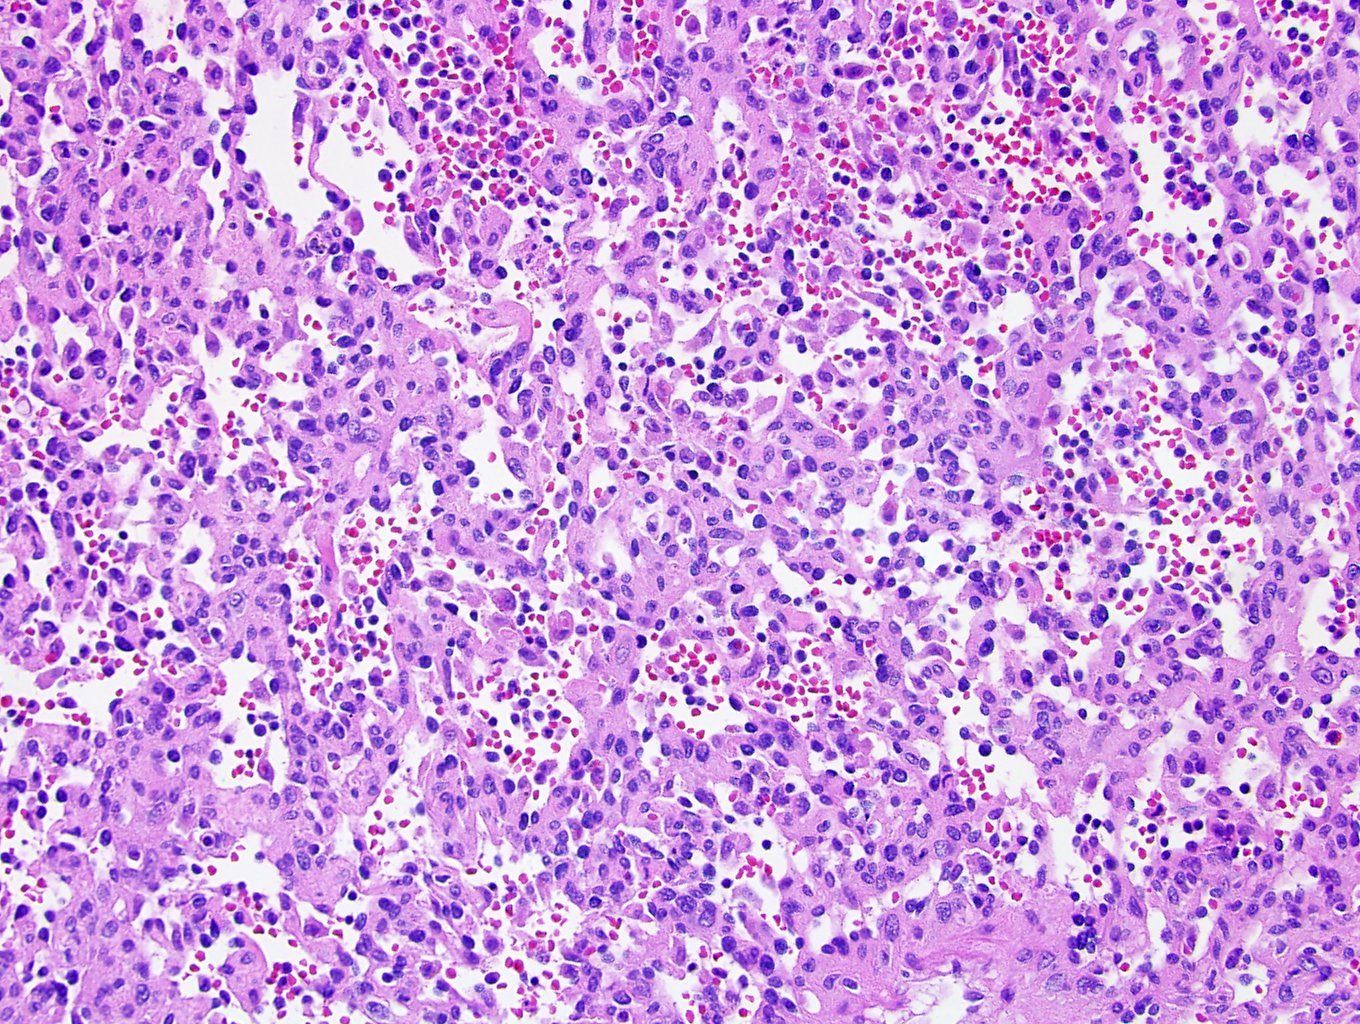

Microscopic (histologic) description

- Circumscribed, unencapsulated proliferation of irregular, blood filled vascular spaces lined by a single layer of endothelial cells

- May or may not show lobular growth pattern with large feeding vessels at periphery (Virchows Arch 2012;461:669)

- Multiple subtypes:

- Anastomosing hemangioma (variant of capillary)

- Anastomosing hemangioma (AH):

- Capillary sized sinusoidal vessels with anastomotic arrangement

- Scattered hobnail endothelial cells

- Extramedullary hematopoiesis, fibrin thrombi, extensive perirenal fat entrapment, intravascular growth and mast cells may be seen (Histopathology 2014;65:309)

- Cytologic atypia and mitotic activity rare

- Regressive changes, including hyalinization, cystic changes and fatty overgrowth (Histopathology 2014;65:309)

Microscopic (histologic) images